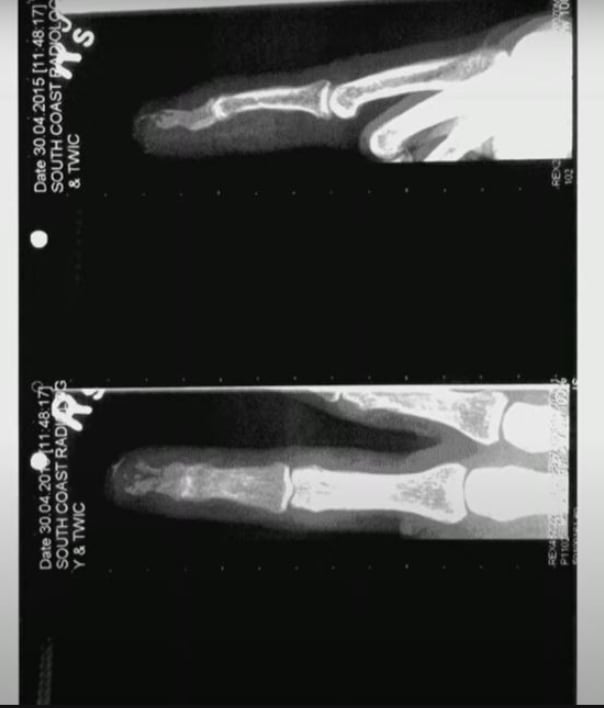

En este sentido, la defensa de Amber Heard presentó radiografías en donde puede verse el hueso aplastado en la punta del dedo.

No obstante, el cirujano afirma que el daño en el dedo de Johnny Depp no fue consistente con el patrón de heridas por corte de botella y, por el contrario, sugiere que se trató de una lesión por aplastamiento.

A su vez, Richard Moore sostiene que la uña de Johnny Depp no presentó daños tras el presunto corte, además de que en los registros médicos nadie anotó que se haya encontrado restos de vidrio en el resto de la mano.